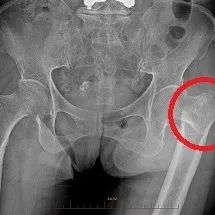

2、股骨粗隆間骨折

術(shù)前

髓內(nèi)釘固定術(shù)后